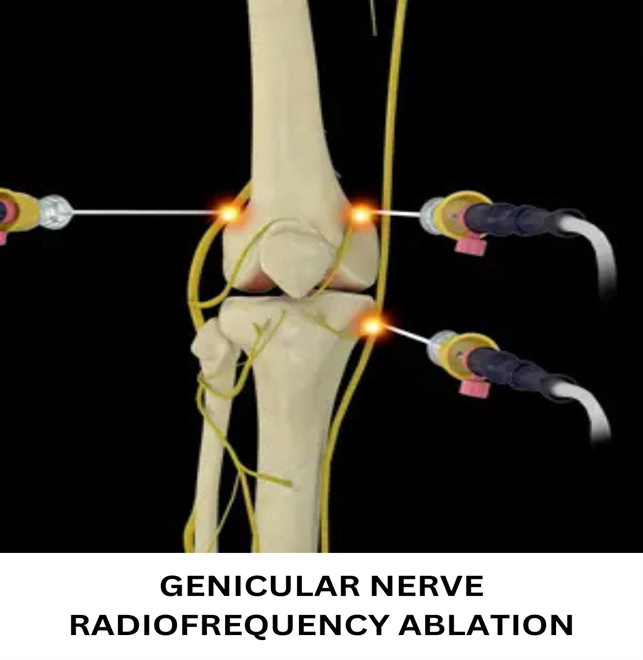

Example 2: Knee pain in osteoarthritis of knee is in part because of synovial inflammation and cartilage degeneration. Nerve supplying the joint are the genicular nerves. We can target the pain generator (synovium and cartilage) by steroid injection that reduces the inflammation and brings relief for 3-6 months depending on the stage of osteoarthritis. PRP injection which is a regenerative therapy can also be given that helps form new healthy cartilage and synovium and brings relief for 9-12 months. Nerve can also be targeted by radiofrequency ablation of the genicular nerves that brings relied for 2.5-3 years. Choice of pain procedure depends on the severity of pain, stage of osteoarthritis and expectations of the patient.

- Nerve ablation techniques: As previously explained, there is a nerve that carries pain from the pain generating structure. Radiofrequency ablation (RF) is a technique that uses heat produced by radio frequency probes set at at a desired wavelength and frequency to selectively damage the pain carrying nerve. It produces a more lasting effect.

- Radiofrequency ablation of genicular nerves:

- Patient selection: Patients with pain of advanced knee osteoarthritis who are not willing for knee replacement surgery benefit tremendously with this technique.

- Technique: Genicular nerves namely superior medial nerve, superior lateral nerve and inferior medial nerve carries the pain of knee. They are ablated by radio frequency energies using an instrument called radio frequency ablation. The procedure is performed in local anaesthesia.

- Expected results: The pain relief last for 2.5-3 years after which the procedure can be repeated.